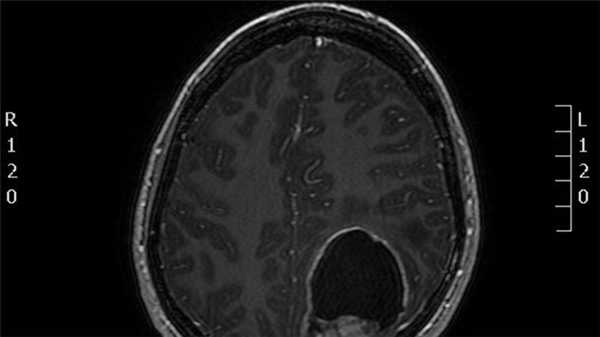

![эпендимома]()

МРТ головного мозга.Т1-взвешенная сагиттальная МРТ. Типичные локализации эпендимомы.

Эпендимома составляет 2-9% от внутричерепных опухолей и 6% от глиом. Из эпендимальных опухолей у взрослых встречается субэпендимома. Она составляет около 8% от эпендимальных опухолей и располагается у стенки желудочка. Пики частоты собственно эпендимомы приходится на возраст 5 лет и 34 года. Опухоль происходит из эпендимоцитов. Обычно это доброкачественные формы. В 60-70% случаев опухоль локализуется инфратенториально в области IV желудочка и в 5-8% в полушариях мозжечка. Гораздо реже обнаруживается супратенториальная локализация эпендимомы: в полушариях вблизи желудочков (на корональных срезах по виду напоминает “цветную капусту”), в области III желудочка, четверохолмия или мосто-мозжечковом углу. Доброкачественные эпендимомы имеют экспансивный тип роста. Внутренняя структура при МРТ неоднородная в связи с кистами (43-83% случаев) и кальцификацией (50% случаев). Контрастное усиление при МРТ наблюдается в трети случаев. Анапластическая эпендимома (градация III) метастазирует по ликворным путям.

Инфратенториальные эпендимомы у взрослых встречаются гораздо реже, чем у детей. Эпендимома встречается в области IV желудочка. Она имеет солидный и кистозный компоненты. При МРТ головного мозга их внутренняя структура часто неоднородная за счёт кальцинатов, кист, гемоглобина и гемосидерина, а также внутриопухолевых сосудов. Эпендимомы часто распространяются через отверстия Лушка и Маженди, что видно при МРТ в корональной плоскости. профессор Холин А.В. имеет большой опыт МРТ в СПб диагностики внутрижелудочковых опухолей мозга в том числе и на открытом МРТ. Среди центров МРТ СПб мы имеем огромный опыт МРТ выявления разных опухолей головного мозга.